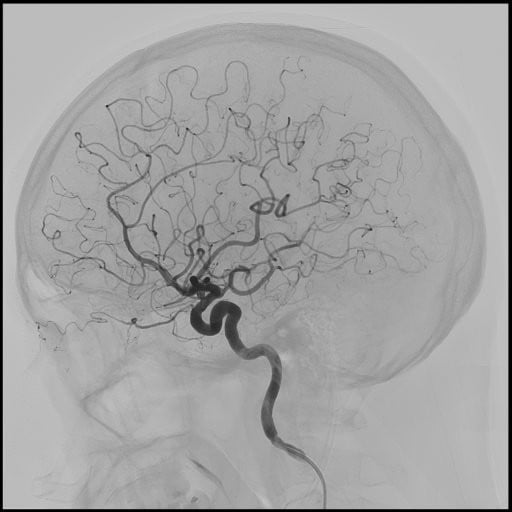

血管造影検査

当院では、血管の状態を詳しく調べたり、カテーテルを使って治療を行う「血管造影検査・治療(IVR)」を実施しています。専用の血管造影装置は2台あり、1台は心臓や足の血管など循環器専用、もう1台は脳や腹部などの頭腹部用です。令和7年4月からは、頭腹部用の装置を最新機種に更新し、より高精度で安全な検査・治療が可能となりました。主な対象疾患は、心筋梗塞、下肢動脈閉塞、脳梗塞、脳動脈瘤、頸動脈狭窄などで、これらに加え、肝臓や子宮の腫瘍、外傷などに対する止血術(TAE)など全身の病気に対応しています。経験豊富なスタッフが担当し、患者さんの負担を軽減しながら、安全で質の高い医療を提供しています。